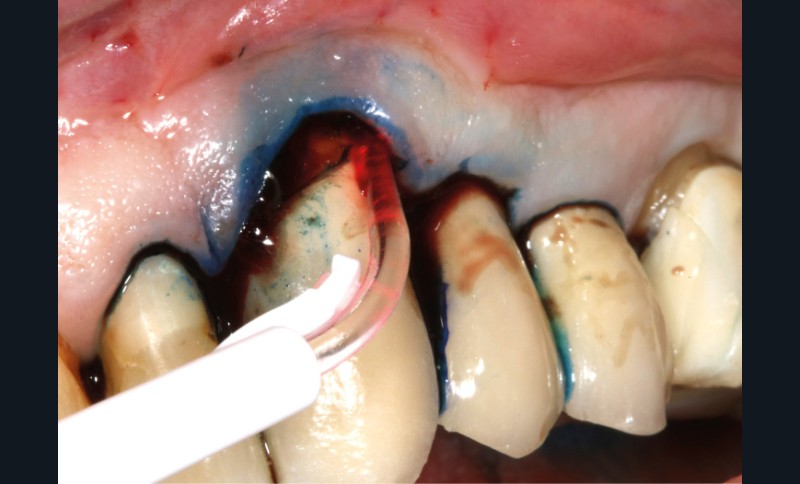

– thérapie photodynamique (bactéricide avec colorant photosensible) pour les lasers de faible énergie (600 à 800 nm),